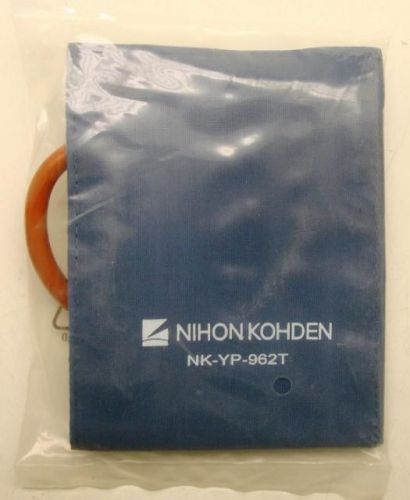

Nihon Kohden NK-YP-962T 18-26cm Reusable Blood Pressure Cuff